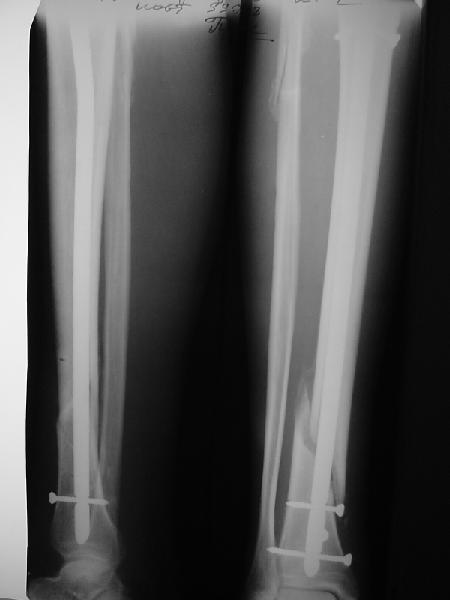

Ok. А также и следующий, в 3 месяца.

Это наглядная демонстрация возможности ранней полной нагрузки при нестабильном по оси повреждении, причем не в самых благоприятных механических условиях - при плохом сопоставлении, со слабым фиксатором.

Покажите, пожалуйста, другие примеры подобных переломов, оперированные с более толстыми запирательными шурупами и дающими полную нагрузку в первый месяц после остеосинтеза.